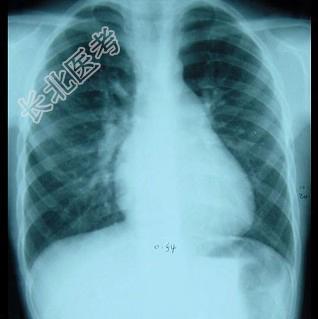

- 单项选择题男性,8岁, 生后发现心脏杂音,位于胸骨左缘第二肋间, 为Ⅲ/6级收缩期杂音,P2亢进, 心电图提示不完全性右束支传导阻滞,于前天拍摄心脏正位片, 如图所示,下面对心脏片描述正确的是 ( )

A、肺血多,主动脉结凸出

B、肺血多,肺动脉段凸出

C、肺血少,主动脉结凸出

D、肺血少,肺动脉段凸出